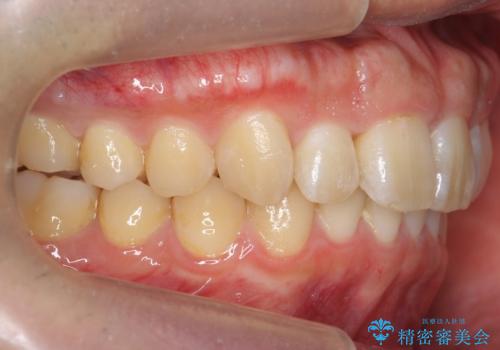

上の歯並びが前方にずれていました。

上顎は歯を抜かずに、奥歯を後ろに下げる治療を行っています。

下顎は歯列を拡大して並べました。